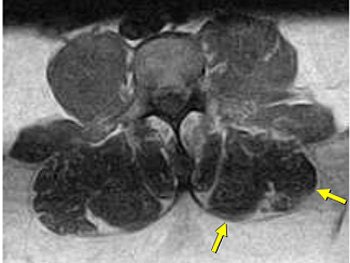

| Same patient as above. Left lateral paraspinal muscle asymmetry indicating deconditioning. Axial-loaded images were obtained with the Portal Gravity System. |